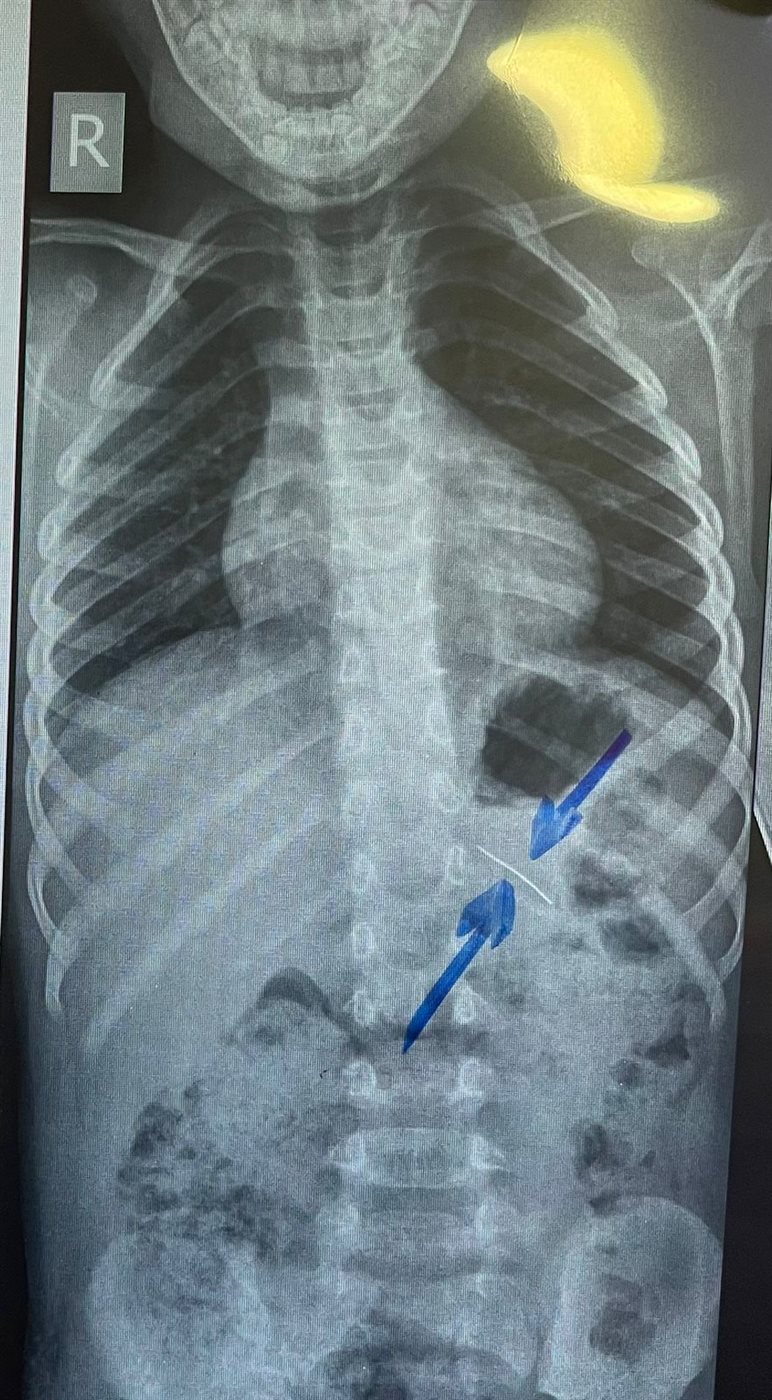

نجح فريق طبي من وحدة أمراض الجهاز الهضمي والكبد ومناظير الأطفال بقسم طب الأطفال بمستشفى سوهاج الجامعي في إجراء تدخل دقيق لاستخراج دبوس من معدة طفل يبلغ من العمر أربع سنوات، باستخدام منظار معدة خاص بالأطفال، دون حدوث أي مضاعفات، وقد غادر الطفل المستشفى بعد ثلاث ساعات فقط من الإجراء، وهو في حالة صحية جيدة.

وأكد الدكتور أحمد كمال، المدير التنفيذي للمستشفيات الجامعية، أن التعامل مع الحالة تم بسرعة وكفاءة، حيث تمكن الفريق الطبي من استخدام المنظار الخاص بالأطفال لاستخراج الدبوس دون أي تدخل جراحي، مما ساهم في خروج الطفل من المستشفى في نفس اليوم بحالة ممتازة.